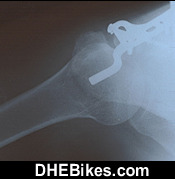

Another shot post surgery photo showing Downhill Dave's right shoulder with the titanium hardware.

This is the after-surgery x-ray of Downhill Dave's right shoulder.

The titanium hardware consists of 6 bolts/ screws and the one big plate.

About a year after the surgery, I actually had to have another surgery to remove the titanium as it was binding in my shoulder and causing extreme pain.